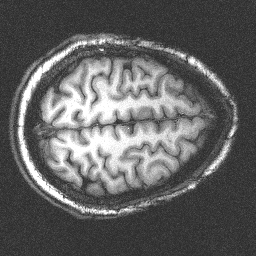

Axial Slice

These are MRI (Magnetic Resonance Imaging) scans of my brain obtained at Brookhaven National Laboratory in 1999. I was a volunteer in a study attempting to correlate brain activity and variable hand gripping strength. My brain showed no activity, but I did learn the meaning of manipulandum.

They actually had trouble shimming my head... I am not kidding, this is what they told me. At one point, my head was misaligned so it appeared as if I had a big hole in my brain. All possible jokes have already been made on this last point...